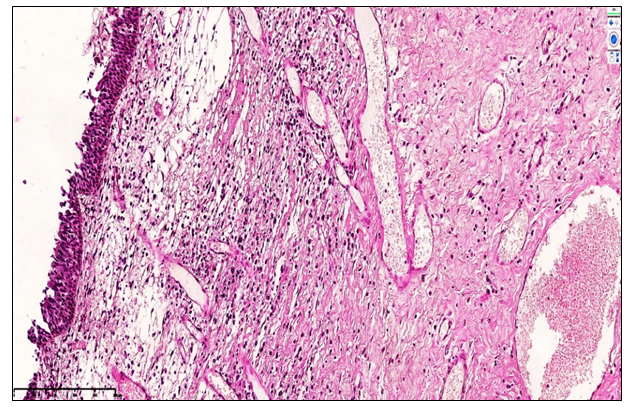

Group 2 (1.5–3 years post-nasal trauma): Morphological analysis revealed that in patients of this group, the secretory activity of the nasal mucosa and submucosa moderately decreased compared to Group 1, reflecting adaptive changes following chronic inflammation. Histologically, the mucosa exhibited mild hyperplastic responses, with proliferation of plasma cells, lymphocytes, macrophages, and hyperplasia of lymphoid MALT structures, leading to limited polypoid growth. The epithelium showed focal metaplasia and irregular multilayered arrangements. Vascular congestion persisted, while stromal mucoid accumulation and lymphoplasmacytic infiltration were observed, accompanied by sparse segmental neutrophils (×200), indicating a lower reactive inflammatory activity relative to Group 1. Overall, polypoid lesions in this group demonstrated reduced mucosal volume and less pronounced inflammatory reactivity, consistent with chronic adaptation of the mucosa (see Figure 5). | Figure 5. Chronic fibrotic nasal polyposis, Group 2 (1.7 years post-nasal trauma): The covering epithelium of the nasal mucosa exhibits mild hyperplasia and focal lymphocytic infiltration, with a sparse presence of neutrophils. Within the glandular stroma, cystic dilations and signs of vascular congestion are observed. Staining method: H&E, magnification 10×10 |